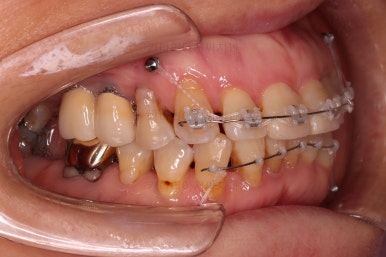

마무리 때의 사진입니다.

부산부분교정 전후사진을 비교해 볼게요.

치열이 매우 가지런해졌고 보이던 틈새도 다 없어졌으며 뻐드러진 느낌도 완벽히 좋아졌어요.

잇몸에서 쑤욱 빠져나와 보이던 치아도 원위치를 찾았고요.

앞니도 약간이나마 뒤로 들어가서 입매도 많이 좋아졌어요.

예휴가 안좋아 뽑아야 될 수 있는 치아는 최대한 아껴아껴 오래 쓰면서 현재 결과가 잘 유지됐으면 좋겠네요.